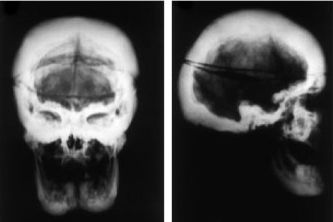

![]() RTG kalvy - nárast kostní hmoty u van Buchemovy nemoci | |

| Klinický obraz | zvýšená produkce kostní hmoty, deformity kostí - hlavně lebky, mandibuly, klavikuly a diafýzy dlouhých kostí[1] |

Van Buchemova choroba je velmi vzácné autozomálně recesivní onemocnění. Na celém světě je popsáno asi 30 případů a z toho přibližně polovina v holandských rodinách[1]. Pacienti trpí hyperostózou. Onemocnění postihuje zejména kosti lebky, mandibuly, žebra, klavikulu a diafýzy dlouhých kostí. Objev mutace pro SOST gen vedl k vytvoření protilátek proti sklerostinu, které se považují za budoucnost léčby osteoporózy.[2]